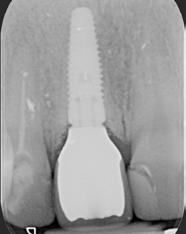

A 2020 januárjában elkezdett kezeléssorozat befejezését az év márciusában, hazánkba is begyűrűző Covid-19 pandémia késleltette, így kb. 6 hónap gyógyulás után láttunk hozzá az emergencia profil és a gingivális zenit ideiglenes koronával történő formázásához (11. és 12. kép). A 3 hetente végzett apró alakításokkal sikerült megfelelő ínyprofilt kialakítani, a „rózsaszín esztétika” a páciens számára is megfelelő volt. A bal felső nagymetsző fog meziális kompozit tömés cseréjét követően, individualizált nyitott kanalas lenyomati fejet készítettünk: az akrilát ideiglenes korona profilját átlátszó szilikonnal lemásoltuk, majd a körszimmetrikus gyári lenyomati fej és az ideiglenes korona kontúrja közötti hézagot folyékony kompozittal töltöttük ki (13. kép). Az így készített egyéni lenyomati fejjel vettünk lenyomatot a végleges, kerámialeplezésű cirkónium-dioxid vázas, átmenő csavaros rögzítésű koronához. (A fogtechnikai munkát Nébl Péter fogtechnikusmester készítette.), (14., 15., 16 és 17. képek).

A kész korona átadásakor a páciens elégedett volt az esztétikával, az azóta eltelt évben rendszeres kontrollokon jelent meg, melyek során meggyőződtünk a kemény- és lágyszövetek stabilitásáról (18. és 19. képek).

17. a–b képek: A kész munka átadáskor. 18. a–c képek: 1 éves kontroll. 19. kép: Intraorális kontroll röntgen felvétele 1 évvel az átadás után.